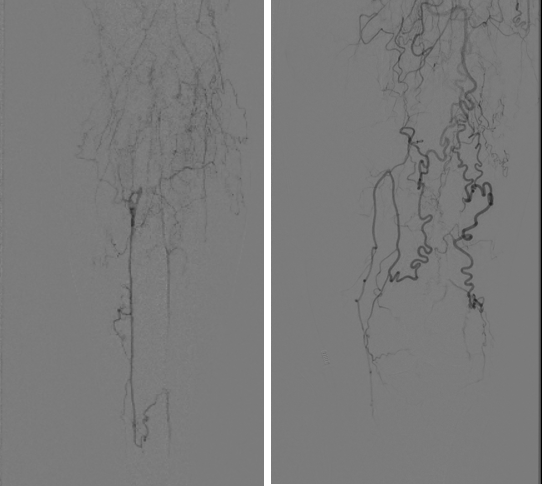

图:术后造影示股腘动脉、腓动脉及足部动脉显影好

手术过程

图:术中CT

手术结果

图:术后效果